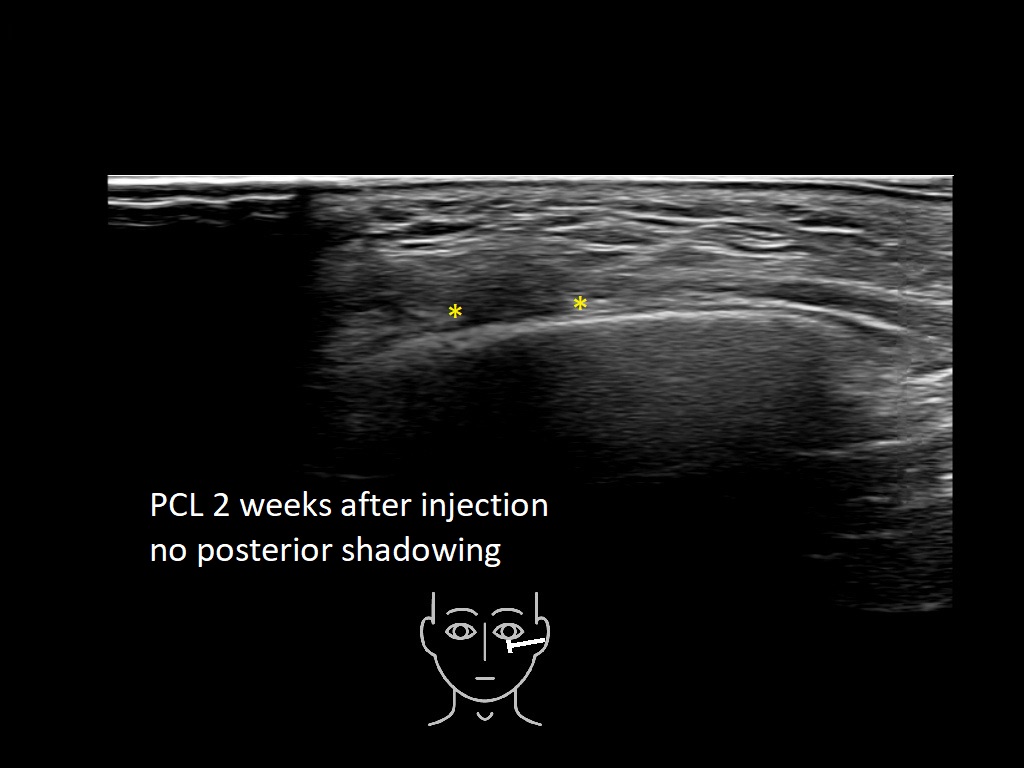

PCL 0

PCL 10a

PCL 11a

PCL 12a

PCL 13a

PCL 14a

PCL 15a

PCL 16a

PCL 1a

PCL 2a

PCL 3a

PCL 3b e

PCL 4a

PCL 4b e

PCL 5a

PCL 5b e